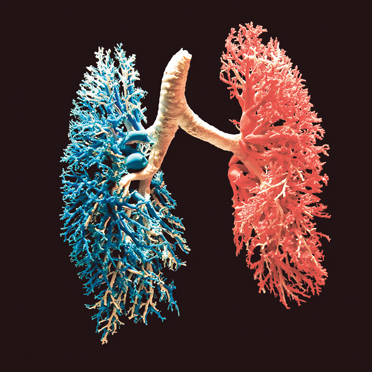

The Human Lungs

Breathing and flow in upper airways Let us take a closer look at the movement...